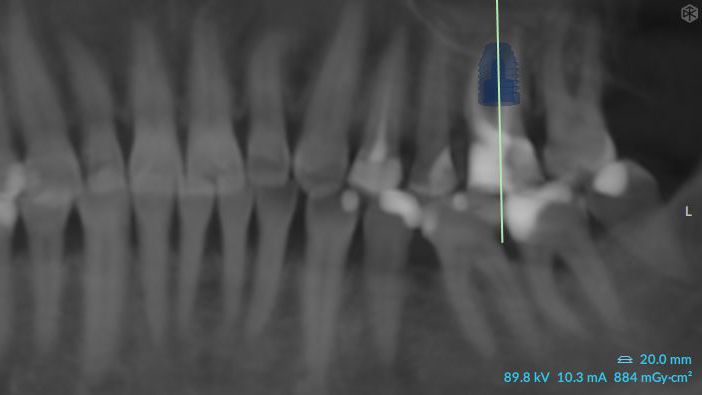

10a. 10b. 10c. 3D scans and radiograph control of the implantplacement.

10a

10b

10c